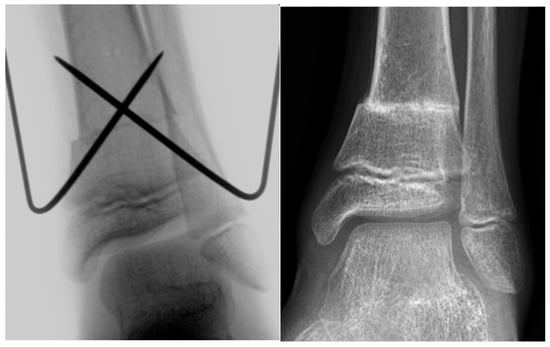

Figure 2.

Intraoperative X-ray image and X-ray image obtained 3 months after SMO fixed with an angular stable plate in a 14-year-old male patient with increased external torsion of the tibia.